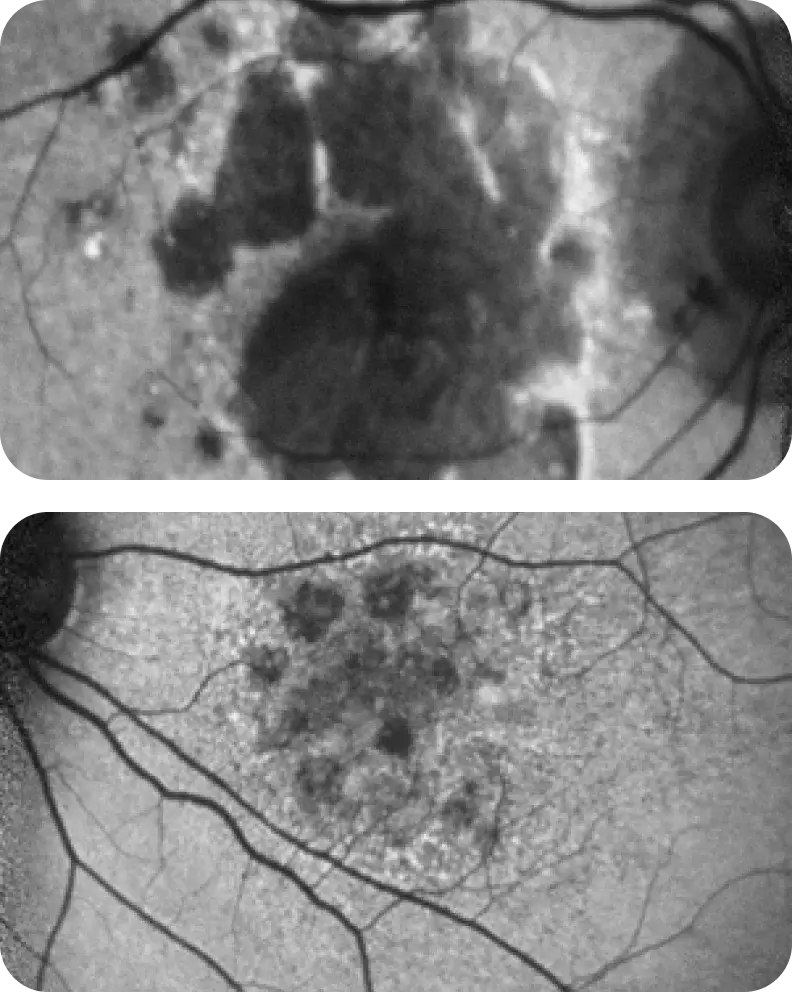

Neovascular AMD

- In clinical trials, use of IZERVAY was associated with increased rates of neovascular (wet) AMD or choroidal neovascularization (7% when administered monthly and 4% in the sham group) by Month 12. Over 24 months, the rate of neovascular (wet) AMD or choroidal neovascularization in the GATHER2 trial was 12% in the IZERVAY group and 9% in the sham group. Patients receiving IZERVAY should be monitored for signs of neovascular AMD.

IZERVAY™ (avacincaptad pegol intravitreal solution) is indicated for the treatment of geographic atrophy (GA) secondary to age-related macular degeneration (AMD)